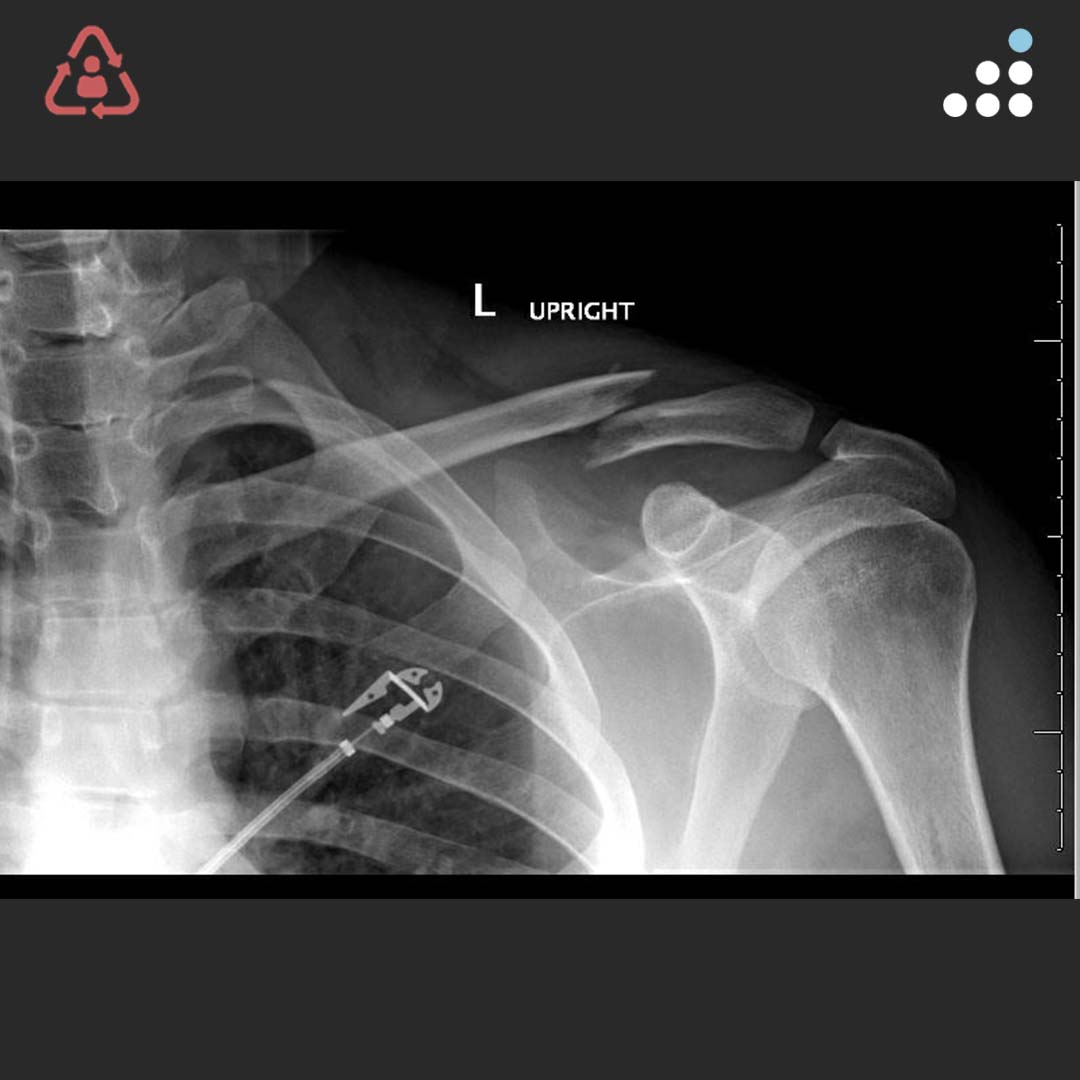

Midshaft Clavicle Fracture Orthobullets . Distal clavicle fractures are traumatic injuries usually caused by direct trauma to the shoulder from a fall in adults. Midshaft clavicle fractures are common traumatic injuries caused by a direct impact to the shoulder girdle and is most. Operative treatment of displaced midshaft clavicle fractures in adult patients is associated with higher union rates and better. Nonoperative treatment of midshaft clavicle fractures. Most surgeons prefer nonoperative treatment of nondisplaced midshaft clavicle fractures. Clavicle shaft fractures are common pediatric fractures that most commonly occur due to a fall on an outstretched arm or direct trauma to lateral aspect of shoulder. However, the optimal treatment option for.

Midshaft clavicle fractures are common traumatic injuries caused by a direct impact to the shoulder girdle and is most. Operative treatment of displaced midshaft clavicle fractures in adult patients is associated with higher union rates and better. Distal clavicle fractures are traumatic injuries usually caused by direct trauma to the shoulder from a fall in adults. Clavicle shaft fractures are common pediatric fractures that most commonly occur due to a fall on an outstretched arm or direct trauma to lateral aspect of shoulder. Nonoperative treatment of midshaft clavicle fractures. Most surgeons prefer nonoperative treatment of nondisplaced midshaft clavicle fractures. However, the optimal treatment option for.